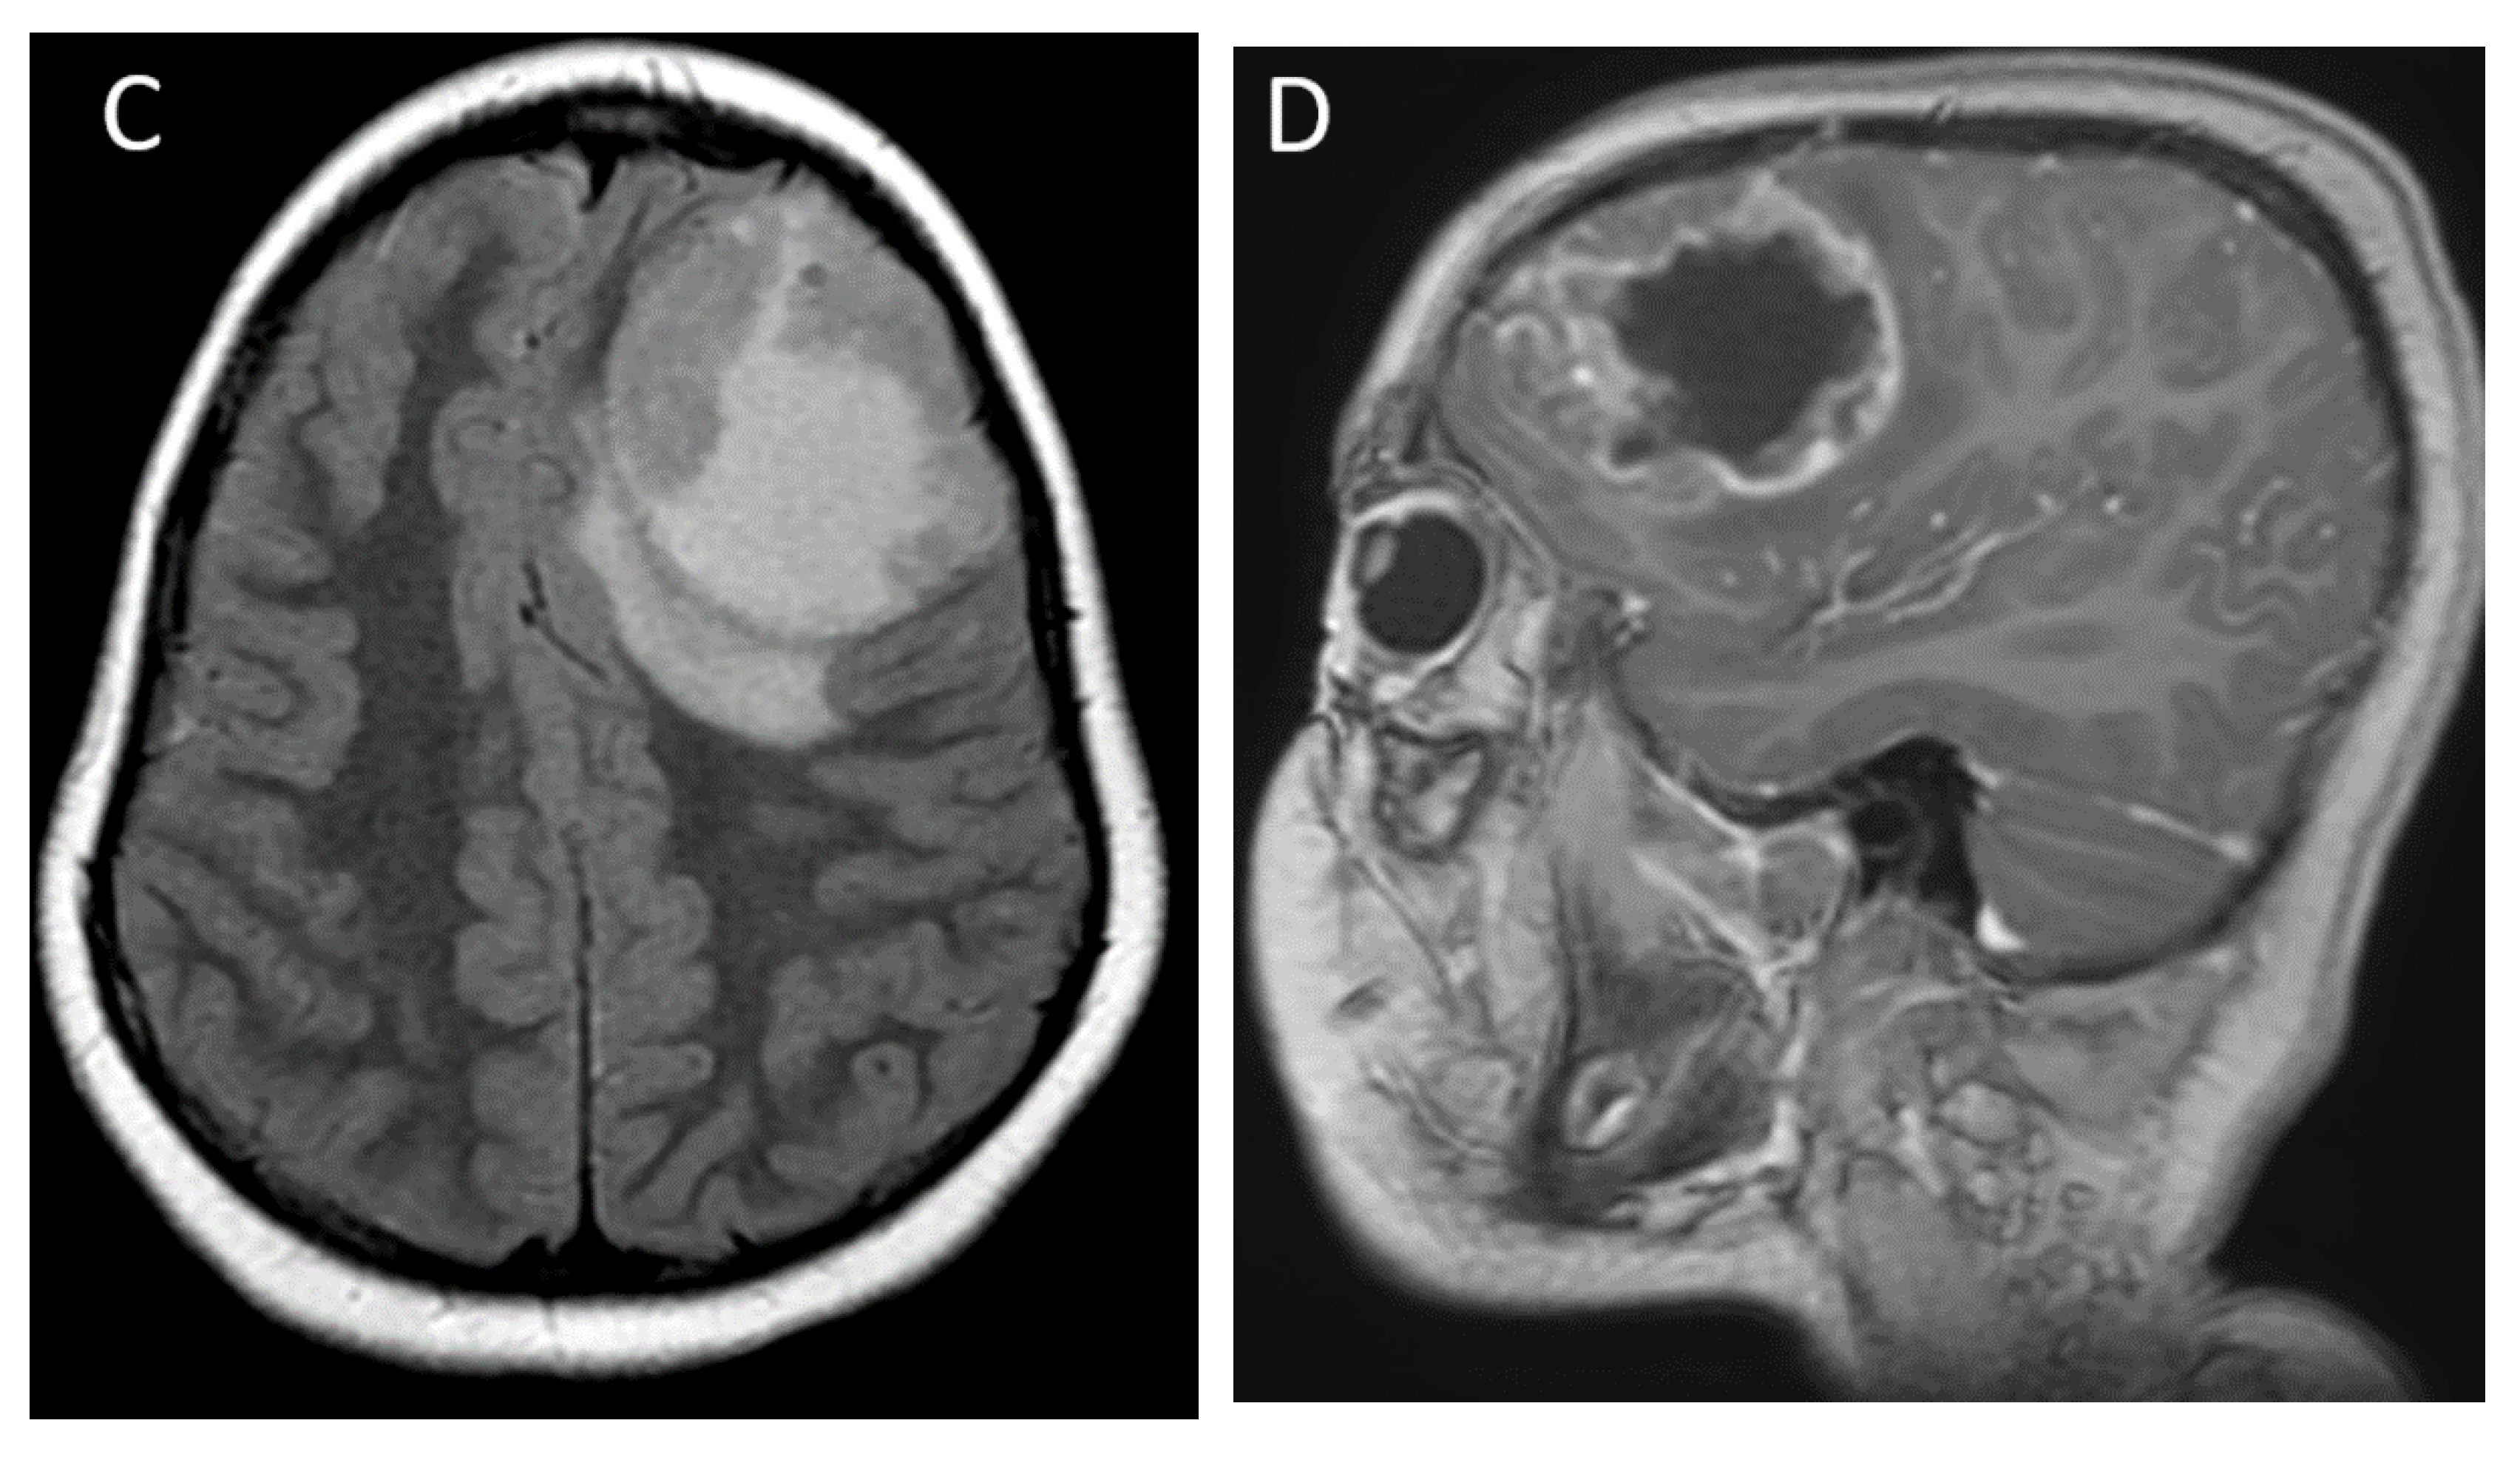

| Supratentorial high-grade glioma (H3 G34 mutant or H3 wild-type) | Hemispheric or deep nuclei; most common in frontal and parietal lobes | Large, circumscribed tumor Diffusion restricting solid components Variable cysts/necrosis and hemorrhage |